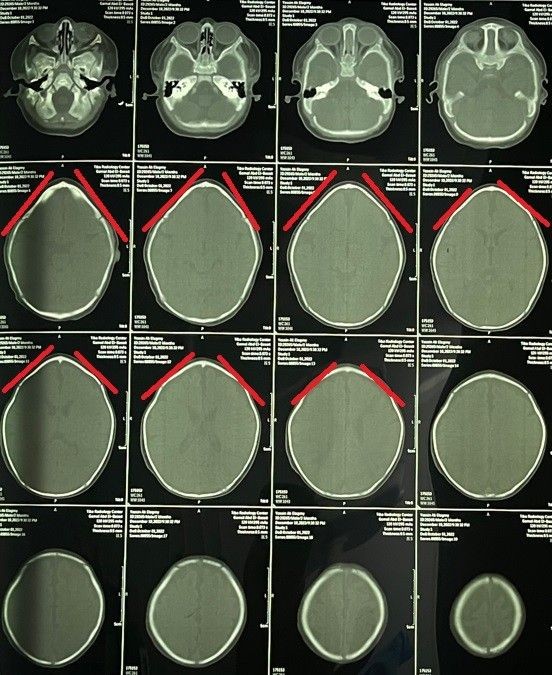

Trigonocephaly Correction Surgery in a Two-Month-Old Infant

A successful cranial correction surgery was performed on a two-month-old infant suffering from trigonocephaly, a condition characterized by a triangular-shaped head. This type of cranial deformity results in a triangular head appearance with a prominent forehead ridge. The goal of the surgery was to correct the skull shape to ensure normal brain development and protect the child from future complications.

• Precise pre-operative planning using 3D imaging